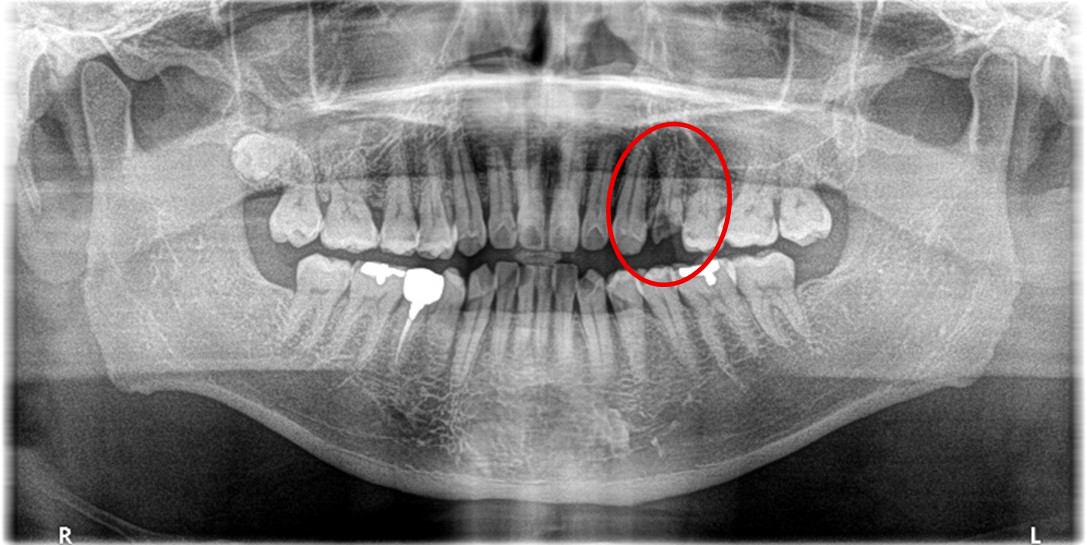

女性 Sさん 50代 (オールセラミック冠)

主訴

左上の差し歯がとれたままになっている。

治療内容

レントゲンを撮り詳しく診てみると、歯根が破折して保存することができず、抜歯する必要があることがわかりました。抜歯後、オールセラミックブリッジで補綴(欠損した部分を人工物で補う)しました。ブリッジの支台になっている後方の歯は、根尖性歯周炎(根の先端で問題を起こしている)でしたので、根管治療をしています。

所感

抜歯後、欠損部分を補う方法には、1本だけの部分入れ歯、ブリッジ、インプラントの3つの方法があります。この患者さんは、ブリッジを選択されました。メタルフリーの治療を希望されましたので、土台をファイバーコアにし、オールセラミックのブリッジをかぶせました。患者さんは、お口の中の金属を徐々に減らしていきたいということです。体全体の健康のことを考えると正しいことです。

オールセラミック冠(失活歯)1本:¥104,500(税込)

オールセラミック冠(生活歯)1本:¥93,500(税込)

ポンティック1本:¥93,500(税込)

合計:¥291,500(税込)